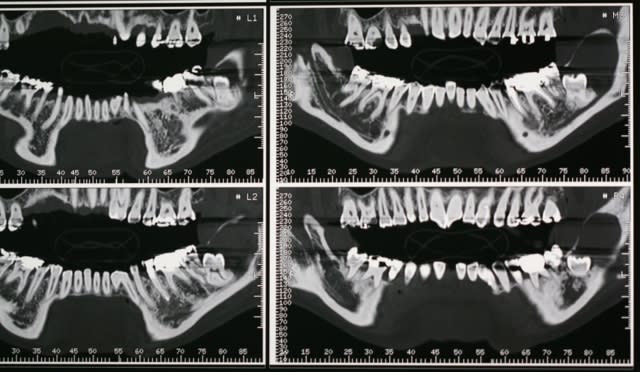

- non je n'ai pas encore l'anapath mais vu la lésion monogéodique uniloculaire, il s'agit à 99% d'un kyste péricoronaire de la DDS.

Je voulais juste préciser qu'il faut pour des kystes aussi important prévoir quand même d'avoir sous la main des ligatures maxillo car pas de possibilité de poser des plaques bien évidemment... pour ton cas c'est je pense différent car d'une part il n'y aucune raison de fracturer et d'autre part on pourrait poser une plaque au niveau de l'angle goniaque car il reste suffisament d'os.

en PJ une radio post-op de kératokyste récidivant où j'ai aussi mis un gros carré de pangen avant de refermer âprès avoir bien cureter